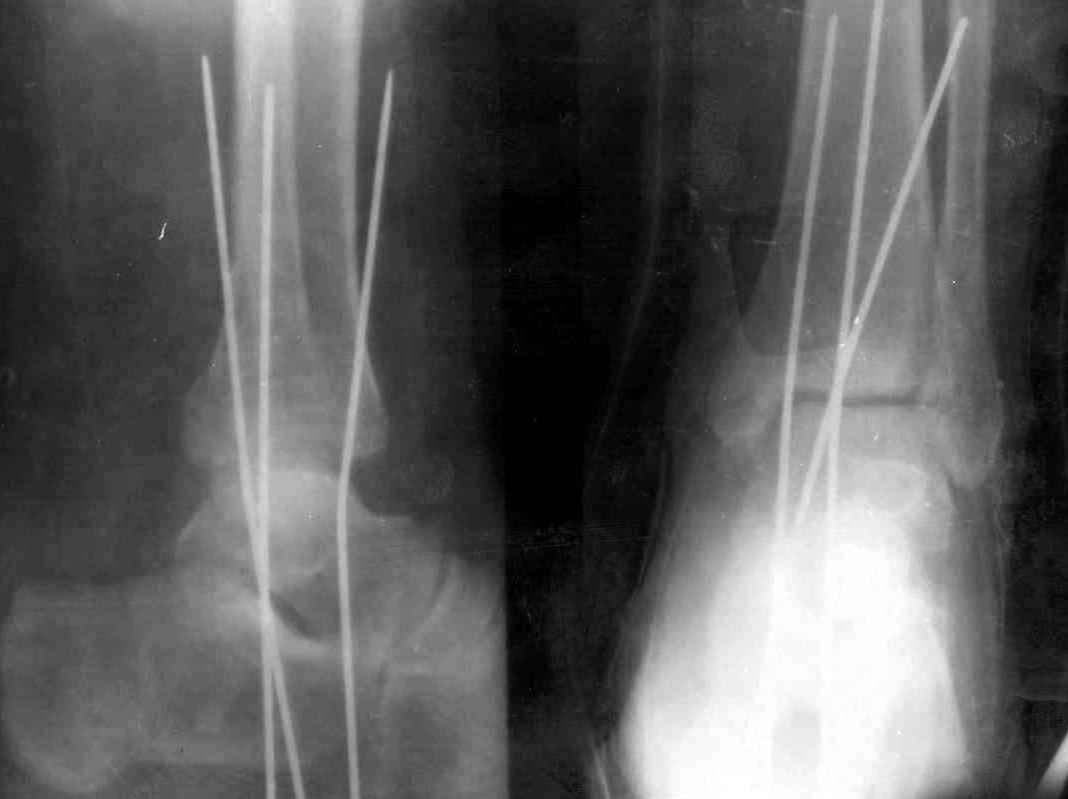

Здесь финальный снимок 73 летней с

сопутствующей шизофренией, латерально бридж

пластину (соединили дистальный конец с диафизом не трогая место перелома) и медиально перкутанно

двумя шурупами. В этам случае без гипса не

обойтись.

Джолдас, Здравствуйте,

Красивые Рг-граммы! У меня нет опыта перкутанной фиксации внутренней лодыжки, поэтому интересно узнать, наблюдали ли вы несращения внутр.лодыжки

Точно, для идеальной репозиции надо открыть передний и задний углы медиальной лодыжки,

сделать ревизию сустава, очистить, убрать интерпозицию, потом только зафиксировать.

Как заметил, по рентгенограмме медиальная лодыжка не очень идеально репонирована. Больная кроме шизофрении страдала другими соматическими заболеваниями, и во время операции от анестезиолога получил рекомендацию поторопиться, поэтому решили закрыто, а так тенденция лечить

открытым методом.